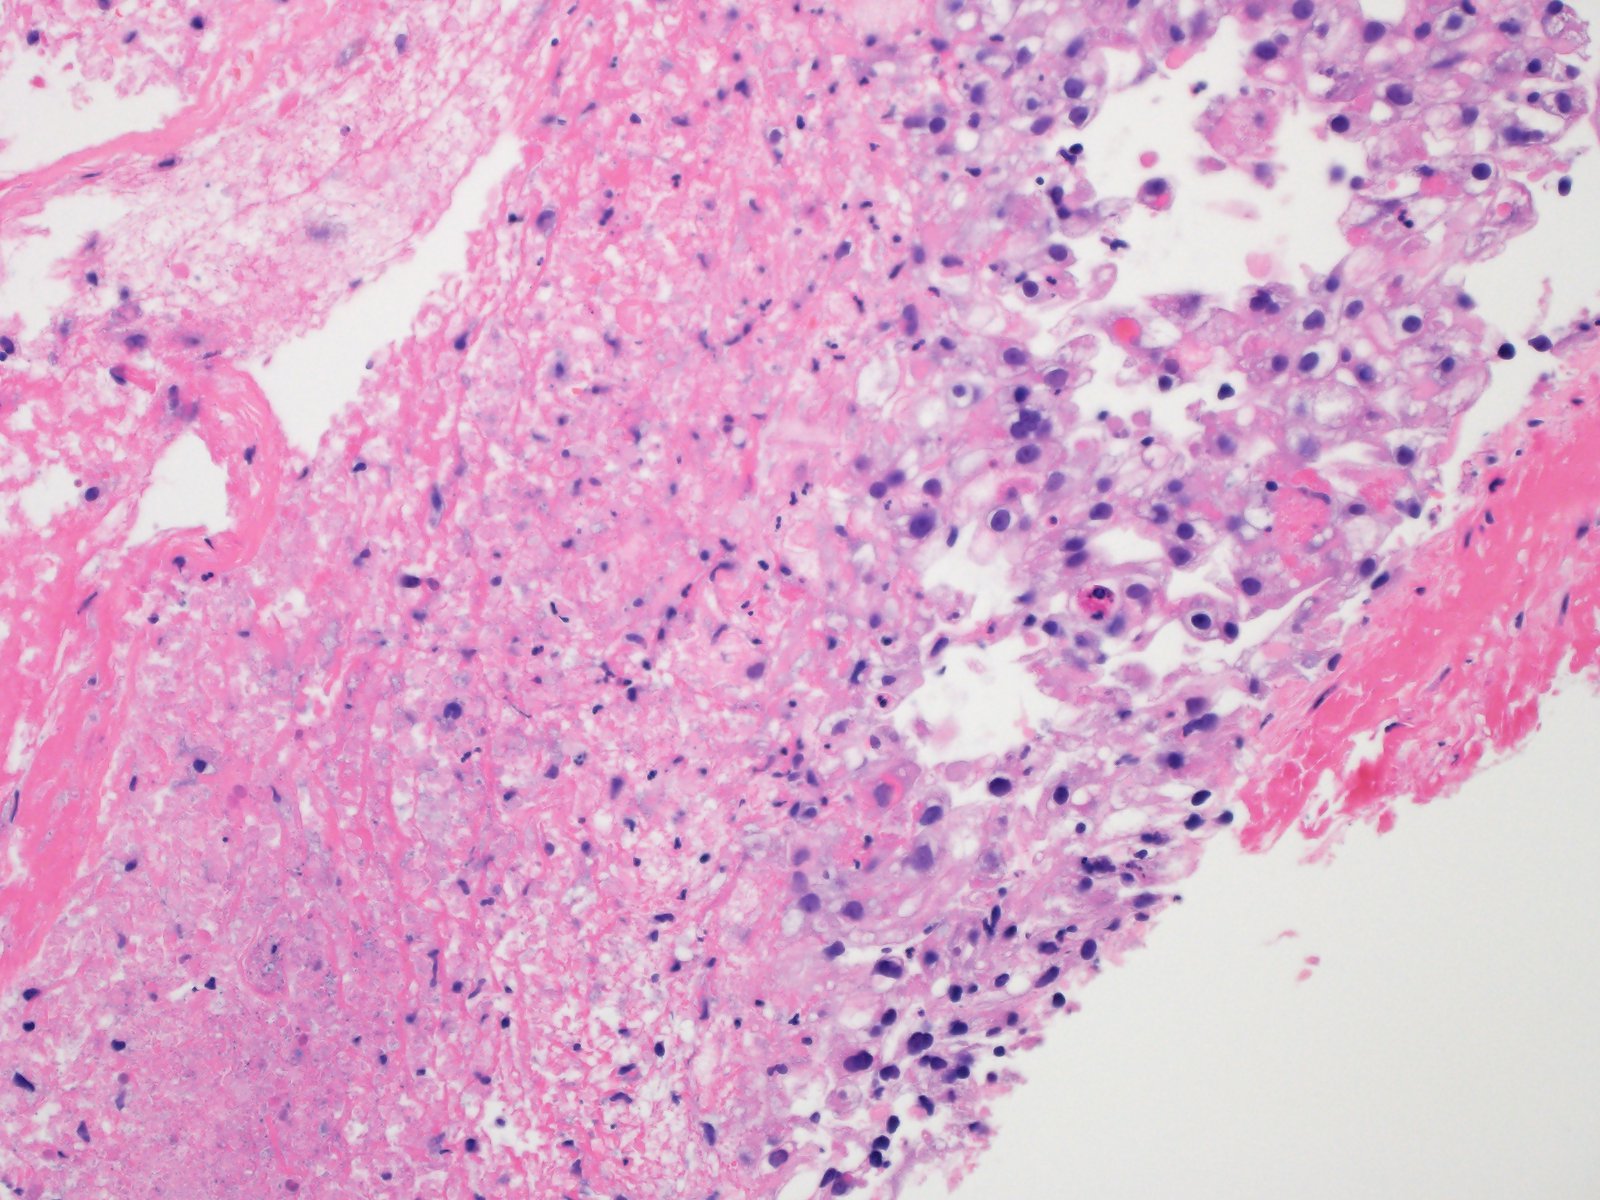

Classification of renal tumors

Case ID: 1059